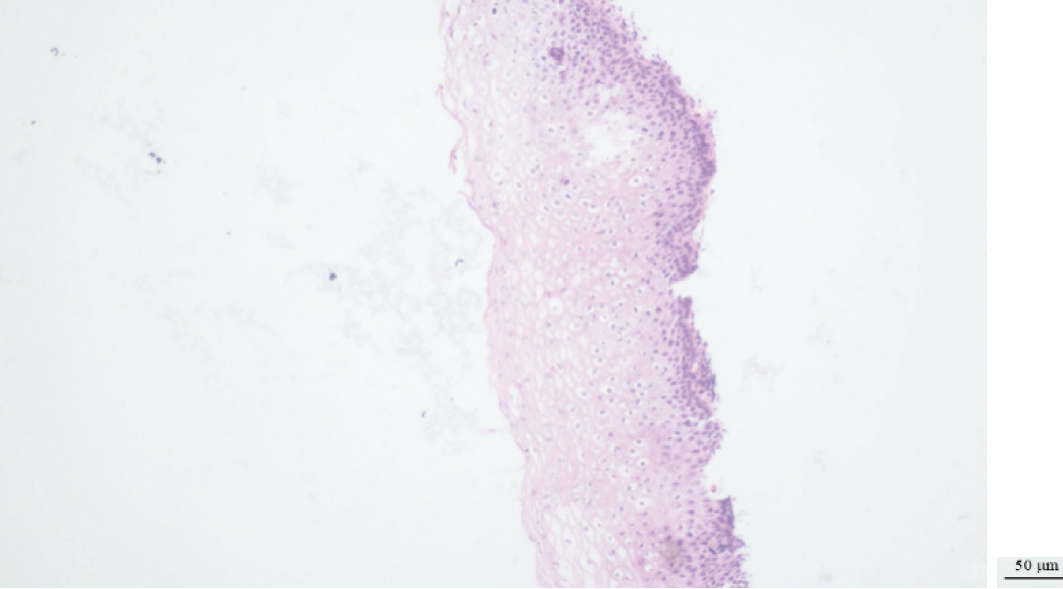

Nguyen DT, Waring D, Wan KM, et al. Superficial and Invasive Spread of High-grade Squamous Intraepithelial Lesion and Squamous Cell Carcinoma: A Case Report[J]. Int J Gynecol Pathol, 2025, 44(3):265-267. doi: 10.1097/PGP.0000000000001062.